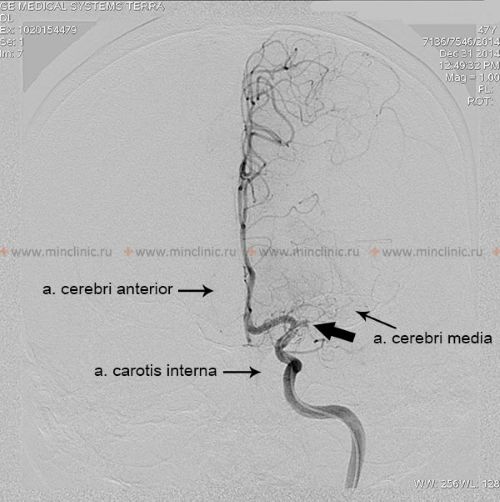

If cerebral artery embolism is suspected, identifying the location of the arterial occlusion and assessing the downstream brain tissue is critical for guiding acute treatment (like thrombectomy) [16, 19]. Non-invasive vascular imaging, such as CT angiography (CTA) or MR angiography (MRA), is typically performed urgently [16]. Conventional catheter-based cerebral angiography (Digital Subtraction Angiography - DSA) provides the highest resolution detail of the vessels but is invasive [14]. It may be performed if endovascular treatment (thrombectomy) is planned or if non-invasive imaging is inconclusive [16, 19]. It's important to note that after several hours or days, an embolus might migrate distally, fragment, or undergo spontaneous lysis (dissolution), meaning that angiography performed later might not show the original occlusion, making the definitive diagnosis of embolic stroke sometimes presumptive based on clinical presentation and infarct pattern [1]. Standard intravenous contrast administration during a routine CT or MRI scan generally lacks the resolution and timing necessary to directly visualize small cerebral emboli within vessels [14].